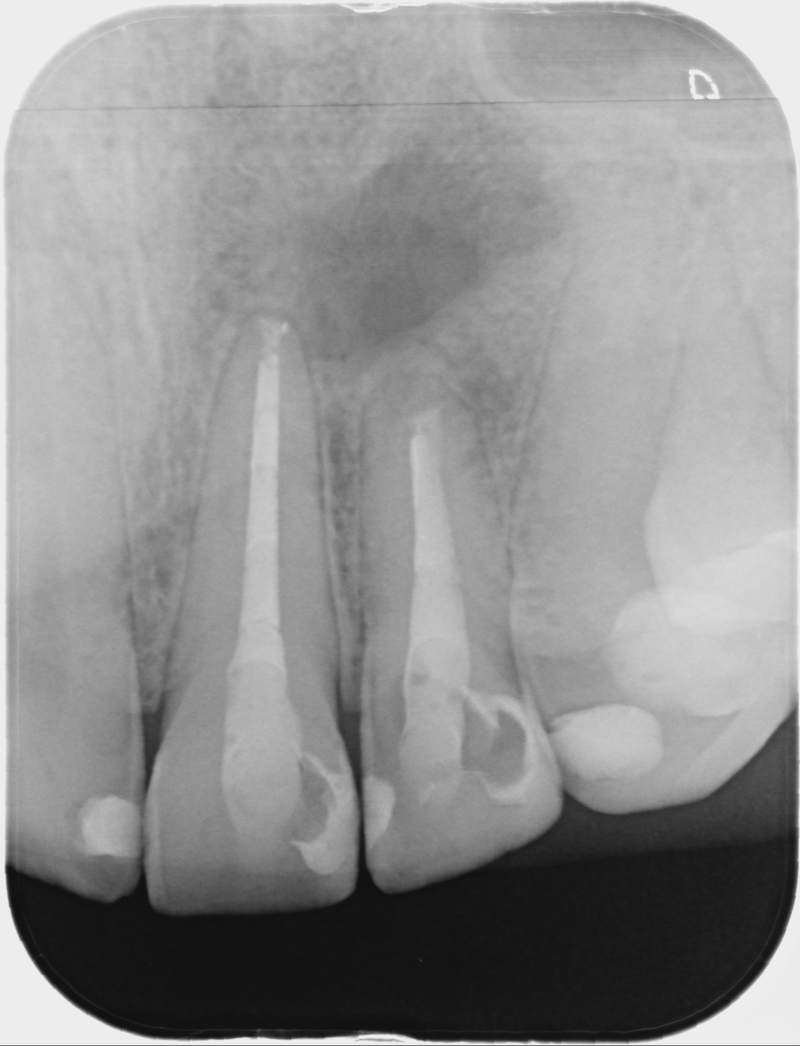

• Klinické vyšetření a rtg 2D a 3D diagnostika v reendodoncii, posuzování kvality předchozího

endodontického ošetření, množství a kvalita tvrdých zubních tkání, vertikální infrakce

a fraktury, resorpce, hluboký aproximální kaz.